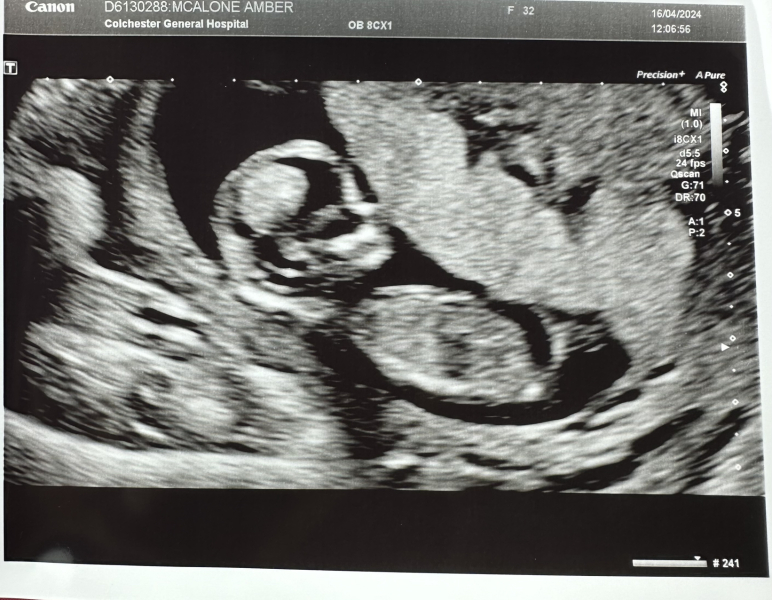

ButterflySkies · 16/04/2024 13:20

Any nub theorists want a guess? 😊

Im 12+5 and due 24 october!

Going to try and relax into this now 🩷

@ButterflySkies I want to say girl, but I have no clue really 🩷

@ButterflySkies girl x